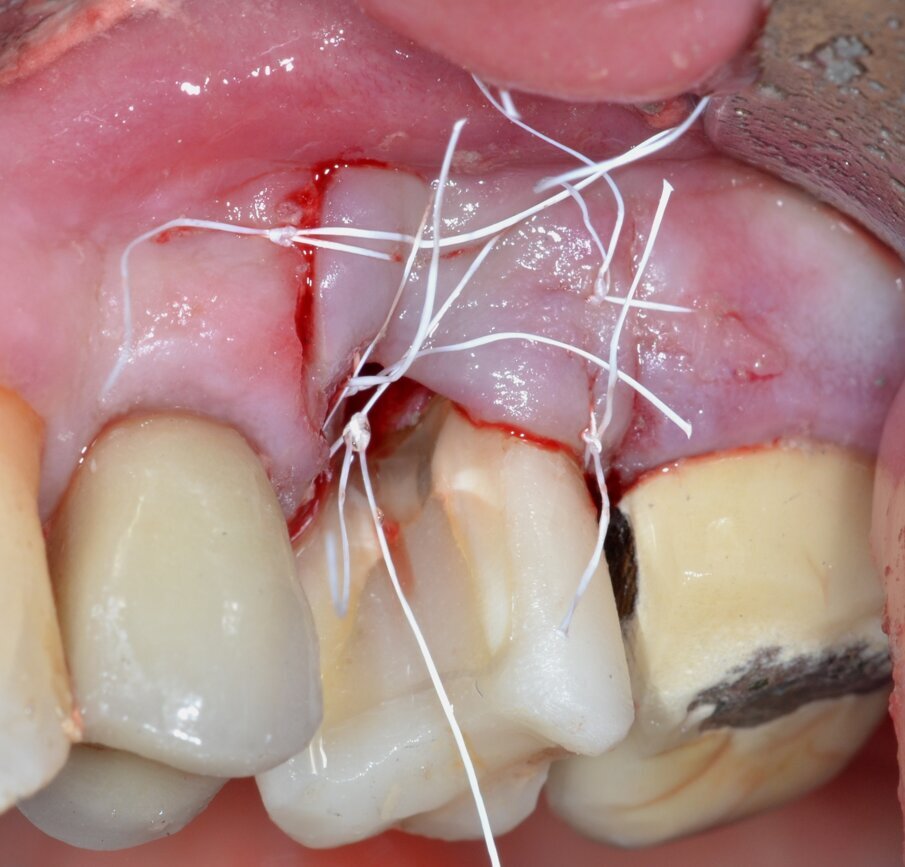

Paziente di aa 56, maschio, giunge alla nostra osservazione lamentando dolorabilità alla palpazione e alla masticazione in corrispondenza dell’elemento 1.6 sottoposto a terapia endodontica diversi anni prima. All’esame obiettivo si rileva la presenza di un’ampia raccolta ascessuale vestibolare associata a una profonda lesione parodontale nella zona della forcazione radicolare buccale (Fig. 1). Il sondaggio nel resto del cavo orale non evidenzia la presenza di altre lesioni parodontali (Fig. 2) mentre l’indagine radiografica rivela la presenza di un’ampia area di radiotrasparenza che coinvolge tutto lo spazio periapicale a partenza dalla radice mesio-buccale (Fig. 3). Sulla base dei dati clinici e radiografici acquisiti viene pertanto confermata la diagnosi di lesione endo-parodontale; nello specifico, si tratta di una lesione endodontica primaria con secondario interessamento parodontale e coinvolgimento della forcazione radicolare di Classe 3 secondo Hamp & Nyman3.

Fig. 1 - Immagine clinica preoperatoria: si evidenzia il coinvolgimento della forcazione radicolare buccale associato a una raccolta purulenta.